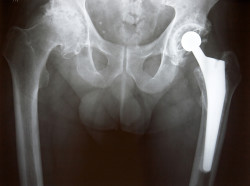

Xray of Left Hip ReplacementAn Arkansas man is seeking compensation after his experience with the Biomet M2A Magnum hip implant ended in hip replacement surgery failure.

According to Doyle’s Biomet lawsuit, the Biomet M2A Magnum hip replacement system is unique among hip replacement implants in that it does not use a liner between the femoral head and the acetabular cup.

Instead, the M2A Magnum uses a “monoblock” system that “forces metal to rub against metal with the full weight and pressure of the human body.”

This design causes the implant to shed particles of cobalt and chromium into the surrounding tissue, Doyle says. The loose metal stimulates the body to attempt to reject the implant, often resulting in pain and looseness or dislocation of the joint.